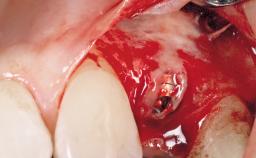

A 30-year-old female patient had lost tooth 21 and was referred to our clinic for consultation and treatment. Due to advanced apical infection, tooth 21 had been extracted two months earlier at another clinic and an acrylic-resin tooth had been bonded to the adjacent teeth. The patient desired implant treatment to avoid any damage to the adjacent natural teeth. While the patient had no history of any systemic disorder, she was a heavy smoker and exhibited medium to advanced periodontitis in the entire jaw. After the initial treatment to achieve a pocket probing depth of less than 4 mm and no bleeding on probing, a decrease in the height of the papillae mesial and distal to the extraction site and overall gingival recession were observed.

Bone Augmentation Horizontal|Staged

Augmentation Materials Autogenous chips|Membrane